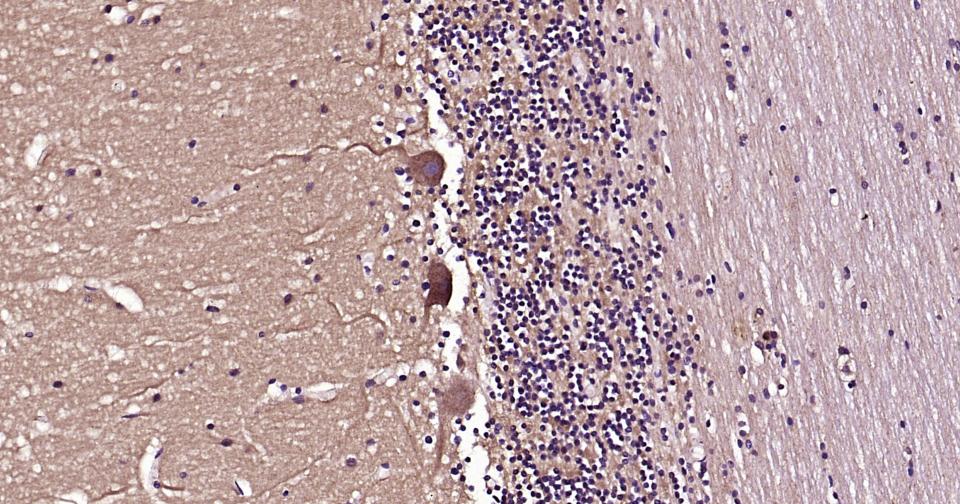

Paraformaldehyde-fixed, paraffin embedded Human Cerebellum; Antigen retrieval by boiling in sodium citrate buffer (pH6.0) for 15 min; Antibody incubation with Beclin 1 Monoclonal Antibody, Unconjugated(bsm-61085R) at 1:200 overnight at 4°C, followed by conjugation to the bs-0295G-HRP and DAB (C-0010) staining.

Paraformaldehyde-fixed, paraffin embedded Rat Cerebellum; Antigen retrieval by boiling in sodium citrate buffer (pH6.0) for 15 min; Antibody incubation with Beclin 1 Monoclonal Antibody, Unconjugated(bsm-61085R) at 1:200 overnight at 4°C, followed by conjugation to the bs-0295G-HRP and DAB (C-0010) staining.

Paraformaldehyde-fixed, paraffin embedded Mouse Cerebrum; Antigen retrieval by boiling in sodium citrate buffer (pH6.0) for 15 min; Antibody incubation with Beclin 1 Monoclonal Antibody, Unconjugated(bsm-61085R) at 1:200 overnight at 4°C, followed by conjugation to the bs-0295G-HRP and DAB (C-0010) staining.

Paraformaldehyde-fixed, paraffin embedded Rat Cerebrum; Antigen retrieval by boiling in sodium citrate buffer (pH6.0) for 15 min; Antibody incubation with Beclin 1 Monoclonal Antibody, Unconjugated(bsm-61085R) at 1:200 overnight at 4°C, followed by conjugation to the bs-0295G-HRP and DAB (C-0010) staining.

Paraformaldehyde-fixed, paraffin embedded Human Cerebrum; Antigen retrieval by boiling in sodium citrate buffer (pH6.0) for 15 min; Antibody incubation with Beclin 1 Monoclonal Antibody, Unconjugated(bsm-61085R) at 1:200 overnight at 4°C, followed by conjugation to the bs-0295G-HRP and DAB (C-0010) staining.